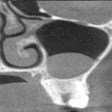

Case #667: 63-year-old man with mandibular lesion